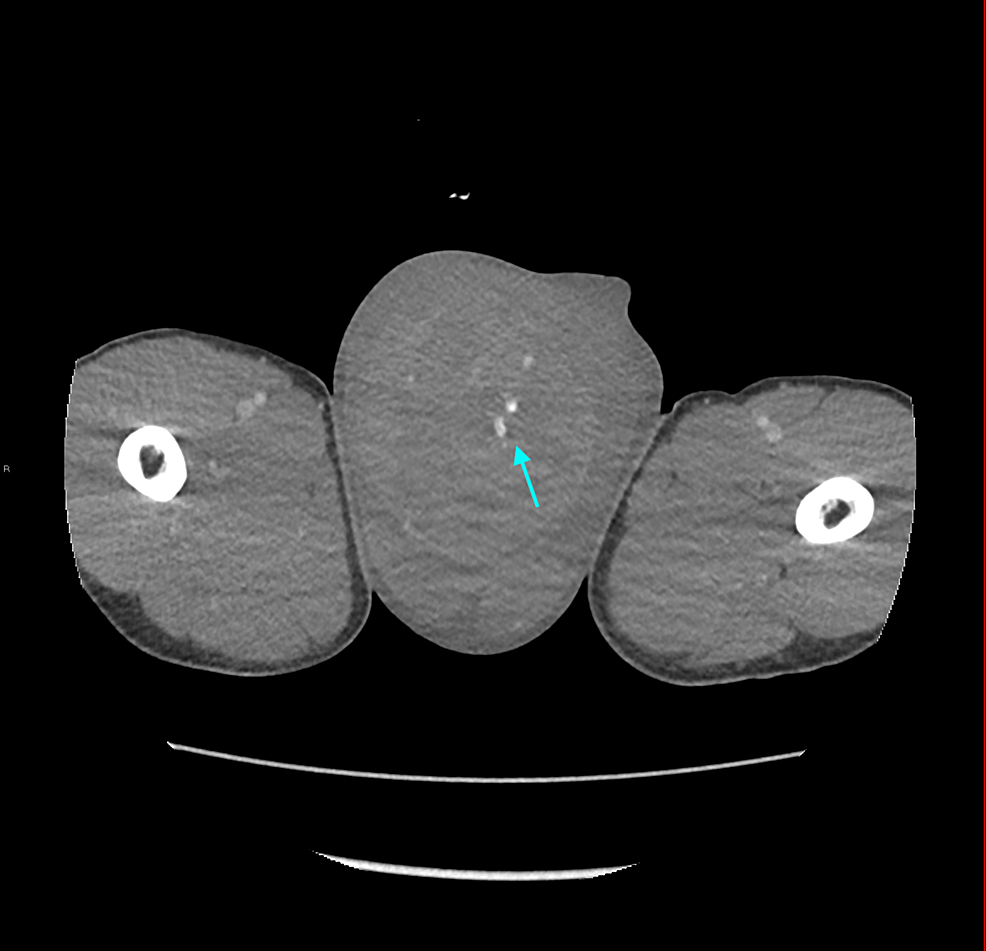

Cureus A Rare Case of Postorchidectomy Arterial Injury With Rapidly Enlarging Scrotal

From www.cureus.com

Cureus A Rare Case of Postorchidectomy Arterial Injury With Rapidly Enlarging Scrotal Coil Embolization Scrotum  It redirects blood away from an enlarged vein in your scrotum. During the procedure the doctor makes a small nick in the skin, (usually in the groin). It redirects blood away from an enlarged vein in your scrotum. Varicocele embolization is a type of medical procedure. Varicocele embolization is a type of medical procedure. Varicocele embolization is a minimally invasive. Coil Embolization Scrotum.

Cureus A Rare Case of Postorchidectomy Arterial Injury With Rapidly Enlarging Scrotal Coil Embolization Scrotum  There are several options for the treatment of varicocele, including surgical repair either by open or microsurgical approach, laparoscopy, or. Coils are commonly used embolic for varicocele, and both detachable and pushable. During the procedure the doctor makes a small nick in the skin, (usually in the groin). Varicocele embolization is an outpatient procedure with a short recovery time. It. Coil Embolization Scrotum.

Cureus A Rare Case of Postorchidectomy Arterial Injury With Rapidly Enlarging Scrotal Coil Embolization Scrotum  During the procedure the doctor makes a small nick in the skin, (usually in the groin). Varicocele embolization is a type of medical procedure. Varicocele embolization is a minimally invasive procedure which is used to treat abnormal enlargement and dysfunctional veins which. It redirects blood away from an enlarged vein in your scrotum. Varicocele embolization is an outpatient procedure with. Coil Embolization Scrotum.

Cureus A Rare Case of Postorchidectomy Arterial Injury With Rapidly Enlarging Scrotal Coil Embolization Scrotum  It redirects blood away from an enlarged vein in your scrotum. During the procedure the doctor makes a small nick in the skin, (usually in the groin). Coils are commonly used embolic for varicocele, and both detachable and pushable. It redirects blood away from an enlarged vein in your scrotum. There are several options for the treatment of varicocele, including. Coil Embolization Scrotum.

Cureus A Rare Case of Postorchidectomy Arterial Injury With Rapidly Enlarging Scrotal Coil Embolization Scrotum  Varicocele embolization is a type of medical procedure. It redirects blood away from an enlarged vein in your scrotum. Varicocele embolization is an outpatient procedure with a short recovery time. Coils are commonly used embolic for varicocele, and both detachable and pushable. It redirects blood away from an enlarged vein in your scrotum. During the procedure the doctor makes a. Coil Embolization Scrotum.

Cureus A Rare Case of Postorchidectomy Arterial Injury With Rapidly Enlarging Scrotal Coil Embolization Scrotum  During the procedure the doctor makes a small nick in the skin, (usually in the groin). Varicocele embolization is a type of medical procedure. It redirects blood away from an enlarged vein in your scrotum. Varicocele embolization is a minimally invasive procedure which is used to treat abnormal enlargement and dysfunctional veins which. There are several options for the treatment. Coil Embolization Scrotum.

Cureus A Rare Case of Postorchidectomy Arterial Injury With Rapidly Enlarging Scrotal Coil Embolization Scrotum  Varicocele embolization is a minimally invasive procedure which is used to treat abnormal enlargement and dysfunctional veins which. Coils are commonly used embolic for varicocele, and both detachable and pushable. There are several options for the treatment of varicocele, including surgical repair either by open or microsurgical approach, laparoscopy, or. During the procedure the doctor makes a small nick in. Coil Embolization Scrotum.

Cureus A Rare Case of Postorchidectomy Arterial Injury With Rapidly Enlarging Scrotal Coil Embolization Scrotum  Varicocele embolization is an outpatient procedure with a short recovery time. Coils are commonly used embolic for varicocele, and both detachable and pushable. There are several options for the treatment of varicocele, including surgical repair either by open or microsurgical approach, laparoscopy, or. During the procedure the doctor makes a small nick in the skin, (usually in the groin). It. Coil Embolization Scrotum.